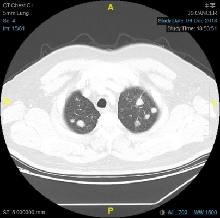

2018-7-19复查CT:两肺多发转移较前增大。疗效PD

2018-07-19: